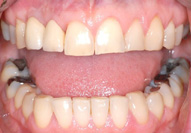

Since 1992, titanium screw implants have been inserted in edentulous sections of the upper and lower jaw in the clinic. Such dental implants serve as artificial tooth roots which, in combination with a tooth-crown-like superstructure (superstructure), enable the restoration of isolated tooth gaps with a crown, in the case of several missing teeth with a crown block, and finally in the case of an edentulous jaw with a fixed prosthesis.

In accordance with the patient's ideas and wishes, conceivable implant-supported prosthetic solutions are presented. In detail, the necessary surgical procedures are explained, the different healing times in the upper and lower jaw are pointed out and, if necessary, the possible later implant-supported dentures are described in consultation with the dentist in charge.